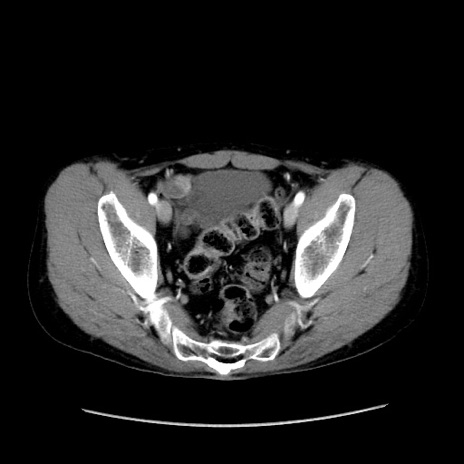

症例37(横断像)

【症例】40歳代 男性

【主訴】腹痛

【現病歴】4時間ほど前に電車に乗車中に臍部上より腹痛出現。徐々に増悪し起立困難となり、救急外来受診。生ものは数日食べていない。今朝お雑煮を食べた。

【身体所見】BT 36.8℃、BP 117/84mmHg、HR 91/min、SpO2 97%、苦悶様、腹部:臍上部広範囲圧痛あり、反跳痛±

【データ】WBC 8100、CRP 0.03